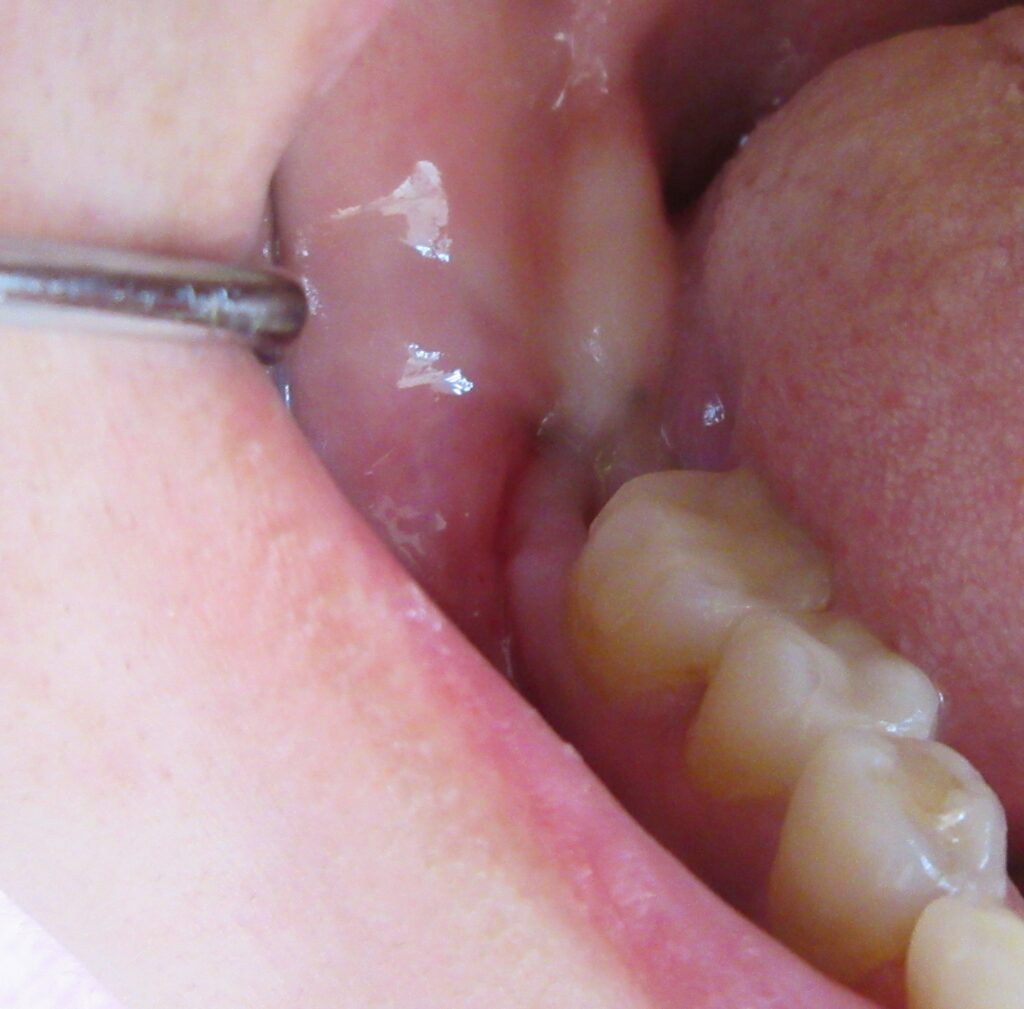

麻酔が効いている事が確認されると、すぐにオペ開始です。

まずは歯茎から骨の部分までを穴開けパンチの要領で穴を開けていきます。

くりぬいた部分の歯肉を取り除き、次は骨に穴を開けていきます。